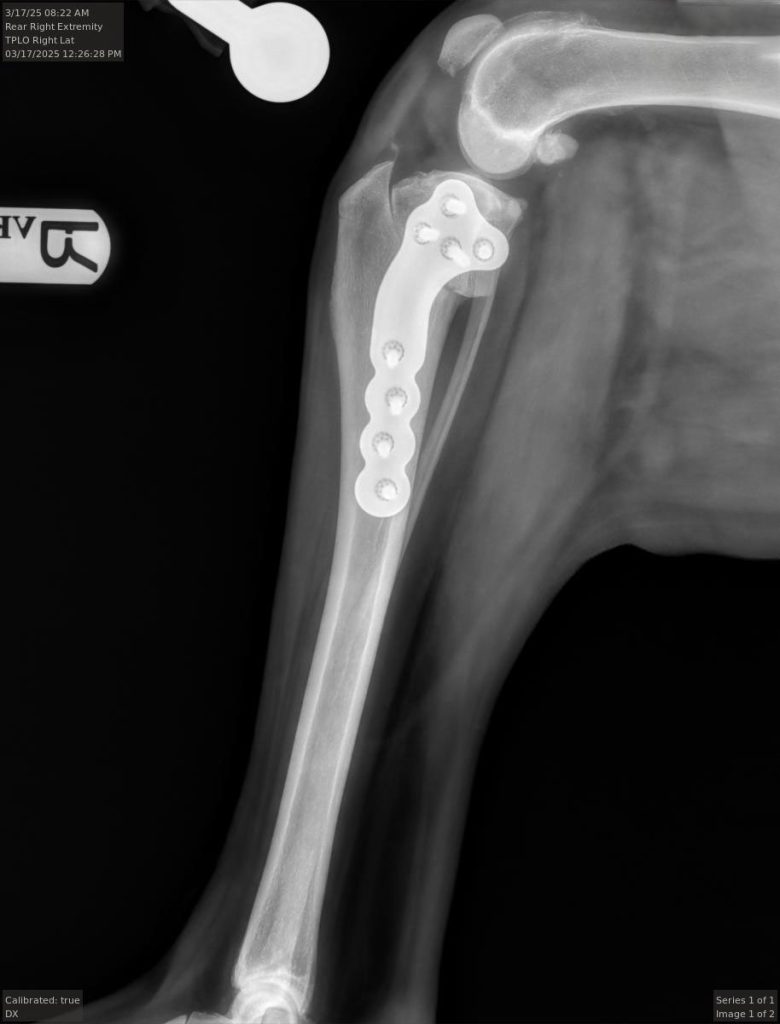

Tibial Plateau Leveling Osteotomy, or TPLO, is a surgery that is commonly performed on medium to large breed dogs suffering from injury, or tear, of the cranial cruciate ligament. This surgery changes the angle of the tibial plateau, alleviating abnormal movement of the tibia that causes pain and discomfort.

The goal of the TPLO surgery is to alter the angle of the tibial plateau, which changes the biomechanics of the knee. This results in the cranial cruciate ligament no longer being needed for stability of the knee. This improves overall function of the knee and alleviates pain during movement.